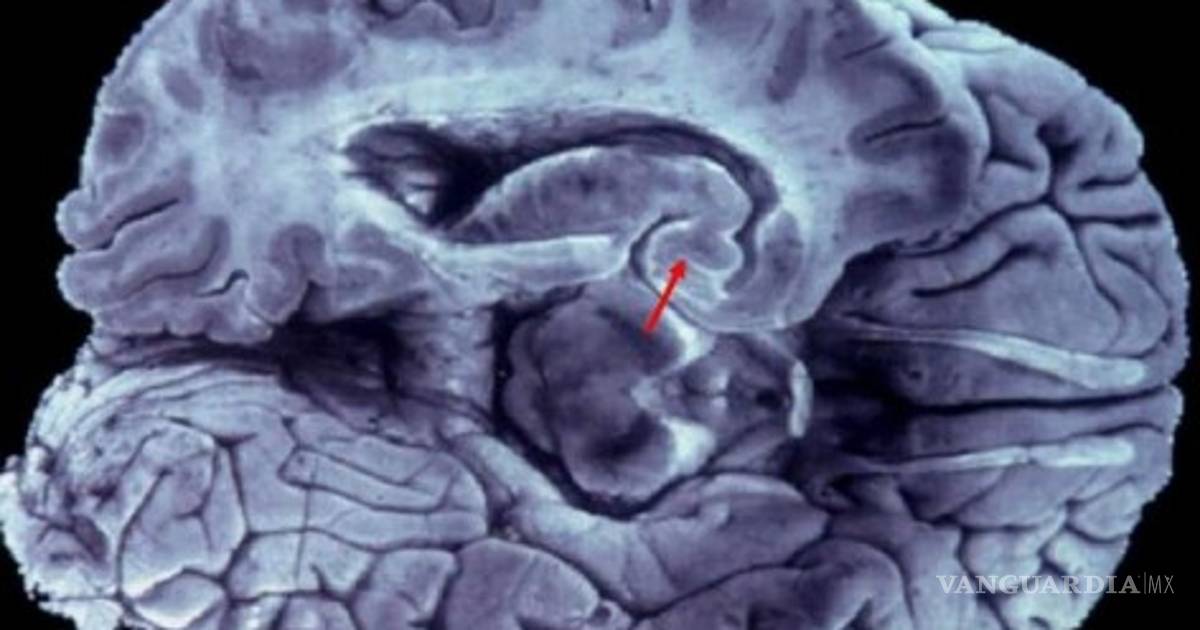

Con el apoyo de las nuevas herramientas, como la resonancia magnética, por ejemplo, es posible medir el volumen de las áreas cerebrales, en particular las involucradas con la memoria y compararlas con las de personas sanas.